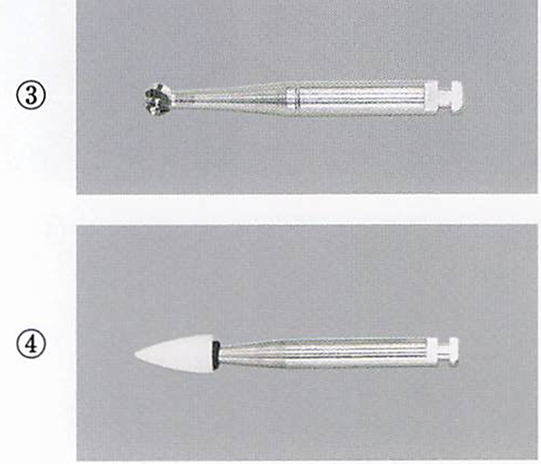

75歳の男性。慢性歯周炎に対する歯周基本治療終了後、3か月間隔で歯周病のメインテナンスと初期の根面う蝕の管理としてフッ化物歯面塗布を行っている。来院時、歯周ポケットの検査を行った後に用いる器材の写真を別に示す。 3番目に用いるのはどれか。1つ選べ。

a. ①

b. ②

c. ③

d. ④

解答を見る

d